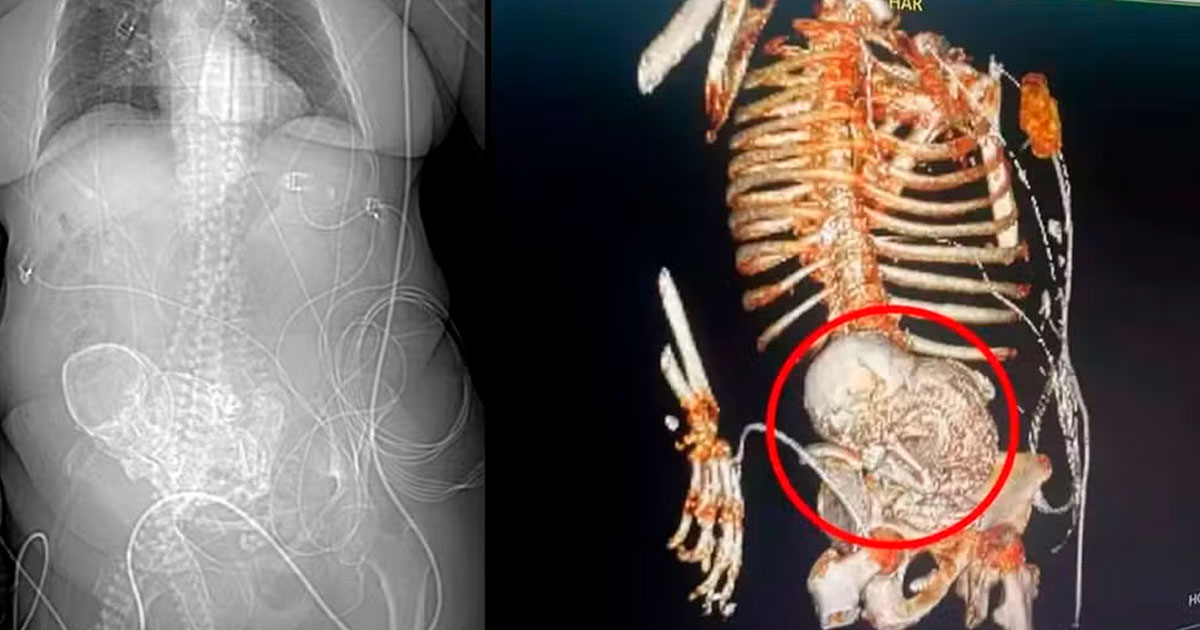

A história de Daniela, que deixou para trás uma família com sete filhos e 40 netos, começou a tomar um rumo inesperado no dia 14 de março, quando dores intensas a levaram ao hospital da região sul do estado. Uma tomografia 3D revelou a presença de um “bebê de pedra” em seu abdômen, um fenômeno conhecido como litopedia, caracterizado pela calcificação de um feto após uma gravidez ectópica não reconhecida. A equipe médica estimou que o feto estava no corpo de Daniela por 56 anos, desde sua última gestação.

Idosa morreu após descobrir bebê calcificado em abdômen. — Foto: Reprodução

O secretário de saúde de Ponta Porã, Patrick Derzi, destacou a raridade do caso, explicando que a litopedia ocorre quando o feto de uma gravidez abdominal morre e se calcifica, podendo permanecer não detectado por décadas e potencialmente causar complicações futuras. Este diagnóstico surpreendente levou à decisão de realizar uma cirurgia de emergência para remover o feto calcificado, um procedimento que, infelizmente, Daniela não sobreviveu. Após a cirurgia, ela foi transferida para a Unidade de Tratamento Intensivo (UTI), onde veio a falecer devido a uma infecção generalizada originada de uma infecção urinária.